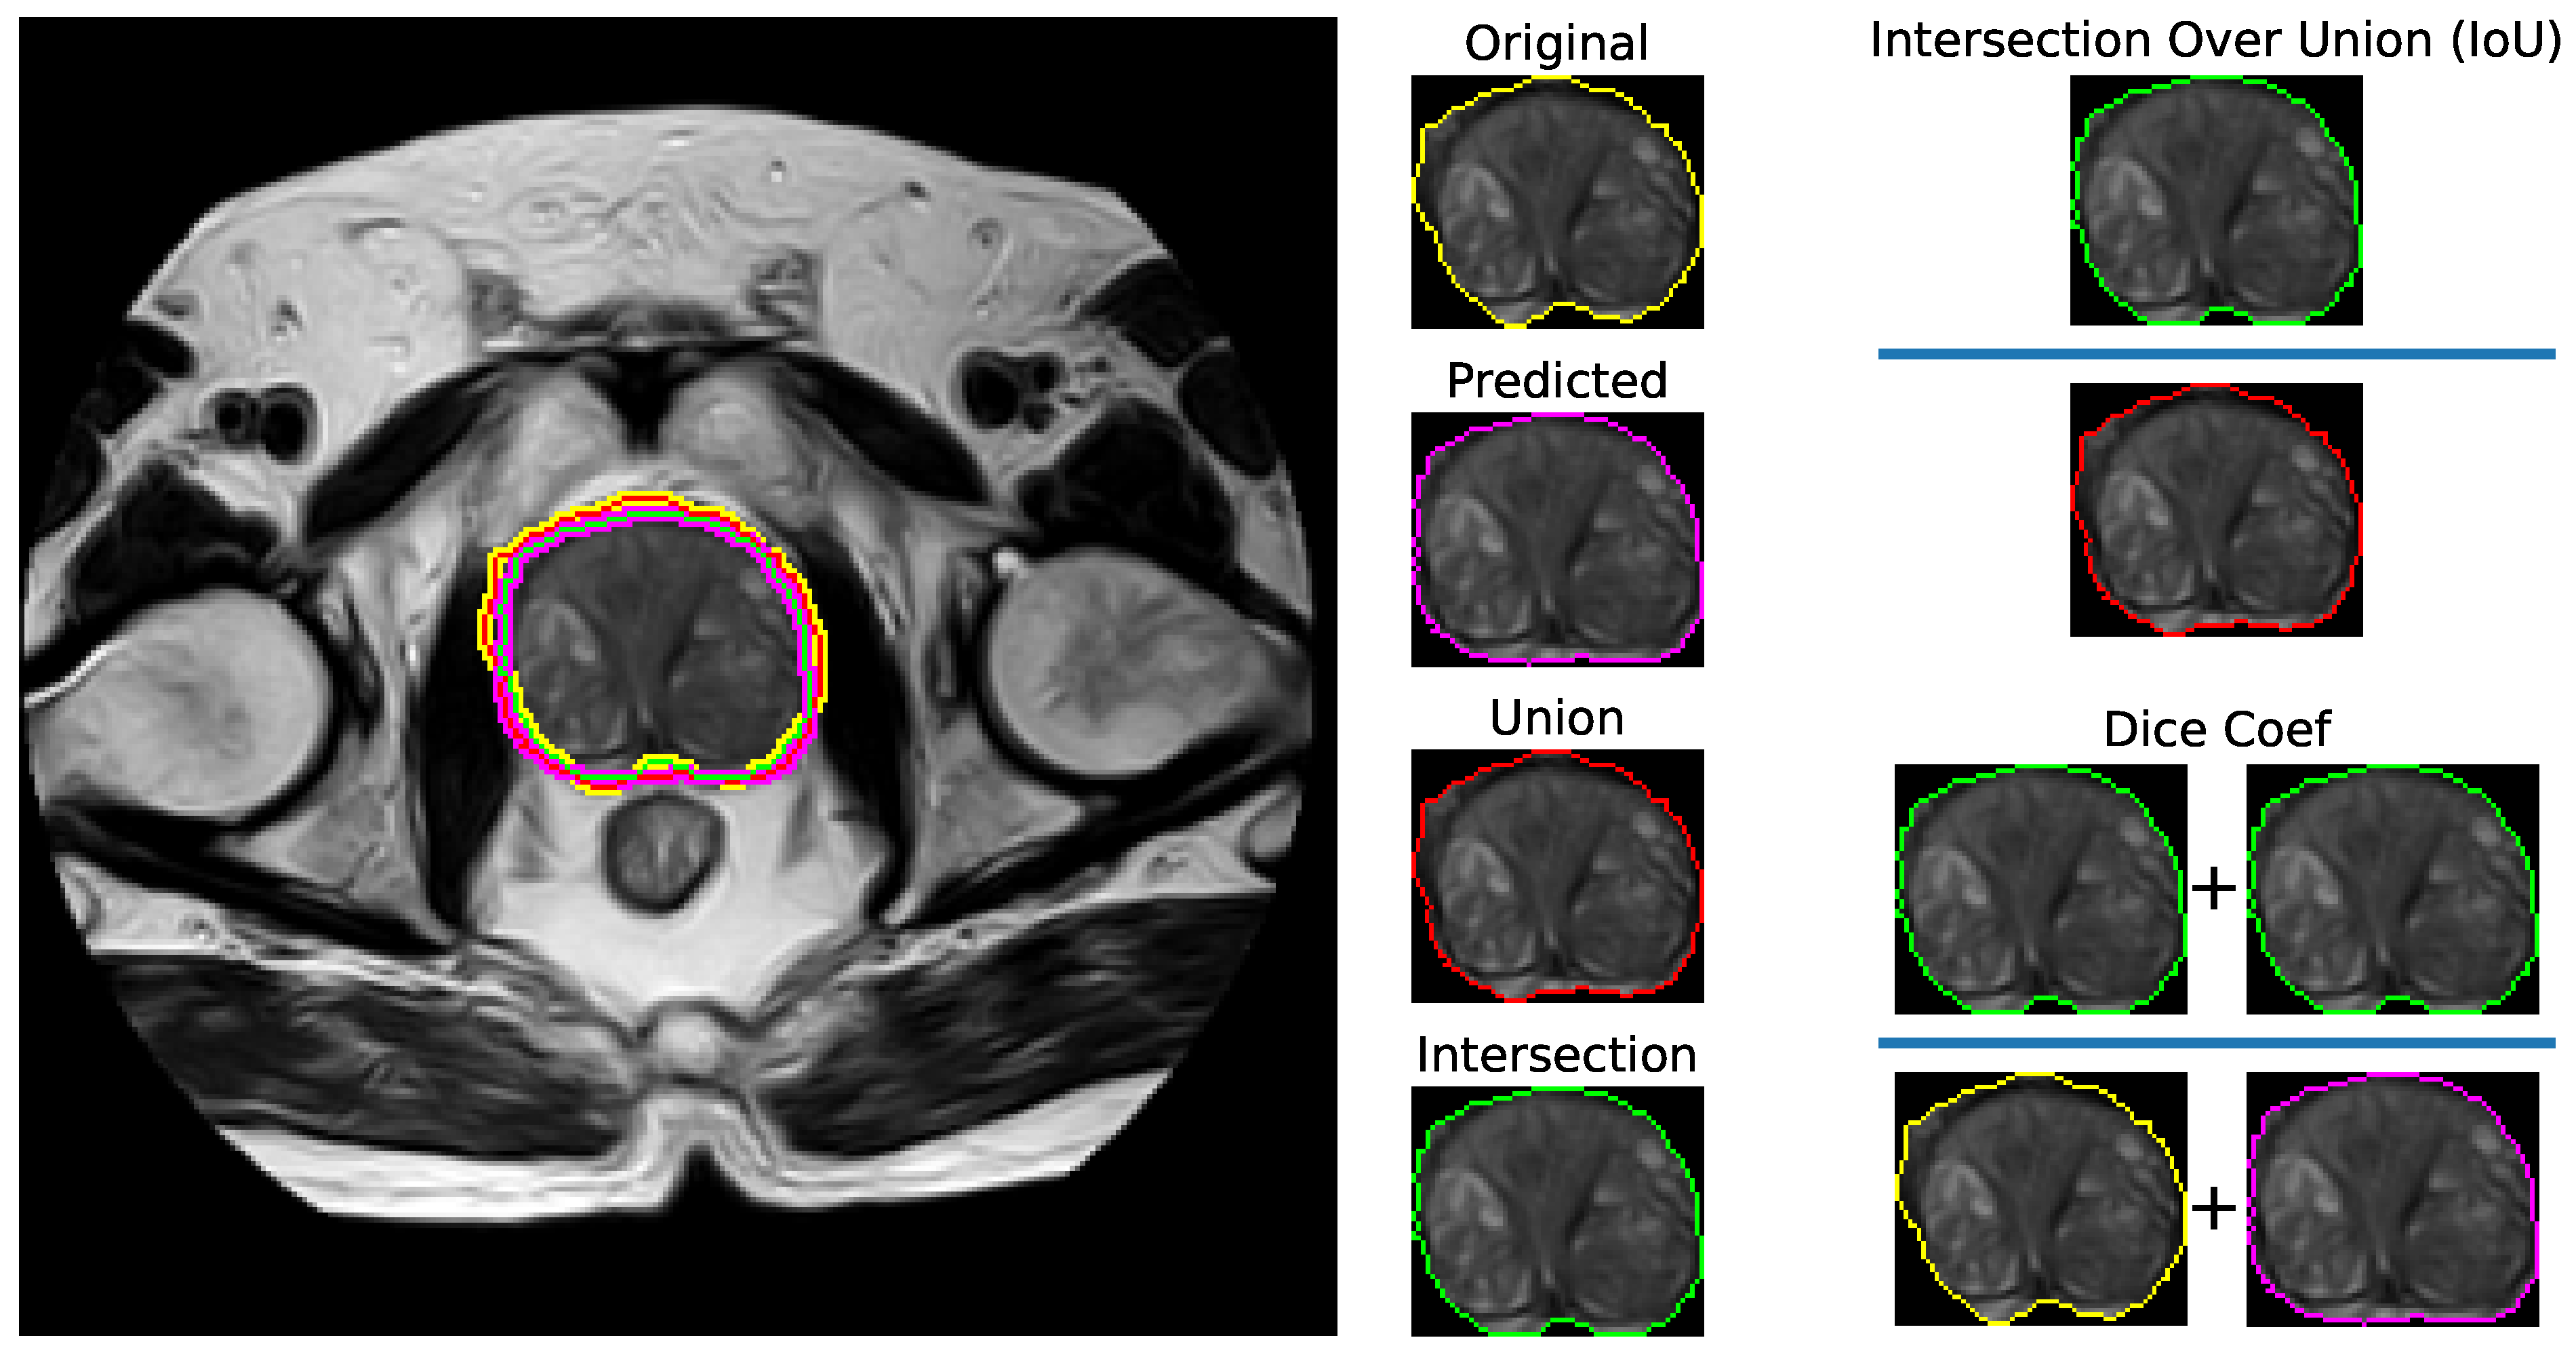

Figure 4 shows a visualization of the Dice coefficient and IoU metrics regarding the segmentation. Figure 5 displays visual examples of the segmented sections for the prostate and lesion accompanied by the corresponding true positives (TP), false positives (FP), and false negatives (FN). The two subplots on the left depict the prostate segmentation, while the four subplots on the right show the lesion segmentation plotted on the whole scan and prostate, respectively. In the images, green indicates FN, blue represents TP, orange indicates TN, and red signifies FP.